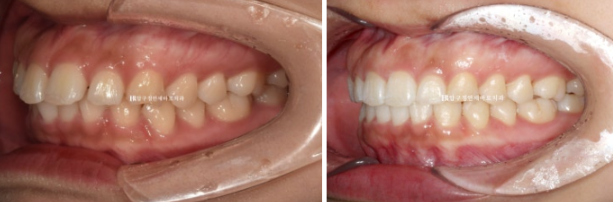

24.02

앞니 좌우 높낮이가 다른 것이 보입니다.

어금니 교합은 좋습니다.

이렇게 어금니 교합이 좌우 I급이면 인비절라인 라이트의 완벽한 적응증입니다.

앞니 사이 벌어진 공간을 모으고 약간의 치간삭제를 동반하여 돌출감도 어느정도 해결하는 것을 목표로 삼았습니다.

24.06

첫번째 세트 장치 14개를 다 낀 후 모습입니다.

모든 것이 좋지만 디테일한 것들을 좀 더 개선하기 위해서 추가장치 제작에 들어갔고 7월부터 10월까지 3개월간 장치를 더 낀 후 마무리 하였습니다.

24.10

뻗쳐있던 앞니 각도는 좋아졌고

24.02~24.10

공간도 깔끔하게 모아졌으며 배열도 좋습니다.

앞니를 뒤로 넣을 때 단순 뒤로만 움직이는 것이 아니라 위로 올리면서 함입하며 넣었기에 잇몸 노출량도 소량 줄었습니다.

일자로 떨어지는 앞니 각도는 세련된 인상을 줍니다